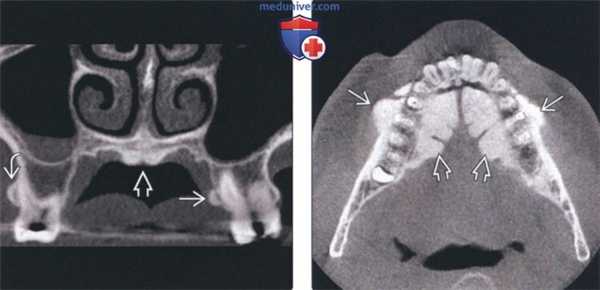

(Слева) На корональной КЛКТ определяются щечный и небный экзостозы в задних отделах верхней челюсти. Небный экзостоз иногда называют верхнечелюстным валиком. Обратите внимание на маленький небный валик, который часто появляется вместе с экзостозами.

(Справа) На аксиальной КЛКТ определяются множественные щечные экзостозы в области премоляров нижней челюсти Присутствуют также выбухающие нижнечелюстные валики. Частота экзостозов наивысшая при наличии нижнечелюстного и небных валиков одновременно.